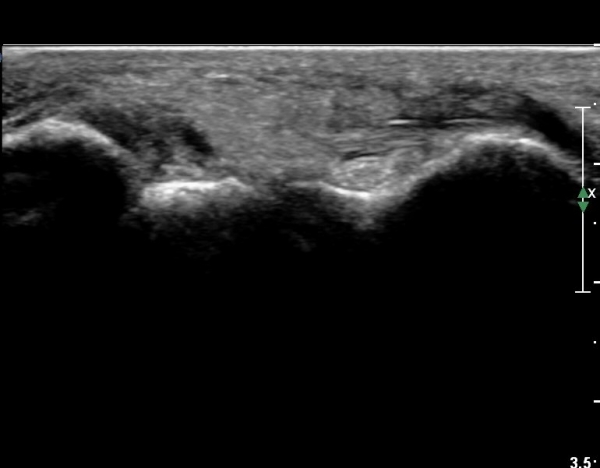

Àü°ÅºñÀδë Á¾´Ü¸é°Ë»ç¿¡¼­  Àü°ÅºñÀδëÀÇ ÆÄ¿­À» º¸ÀÓ(»çÁø 2).